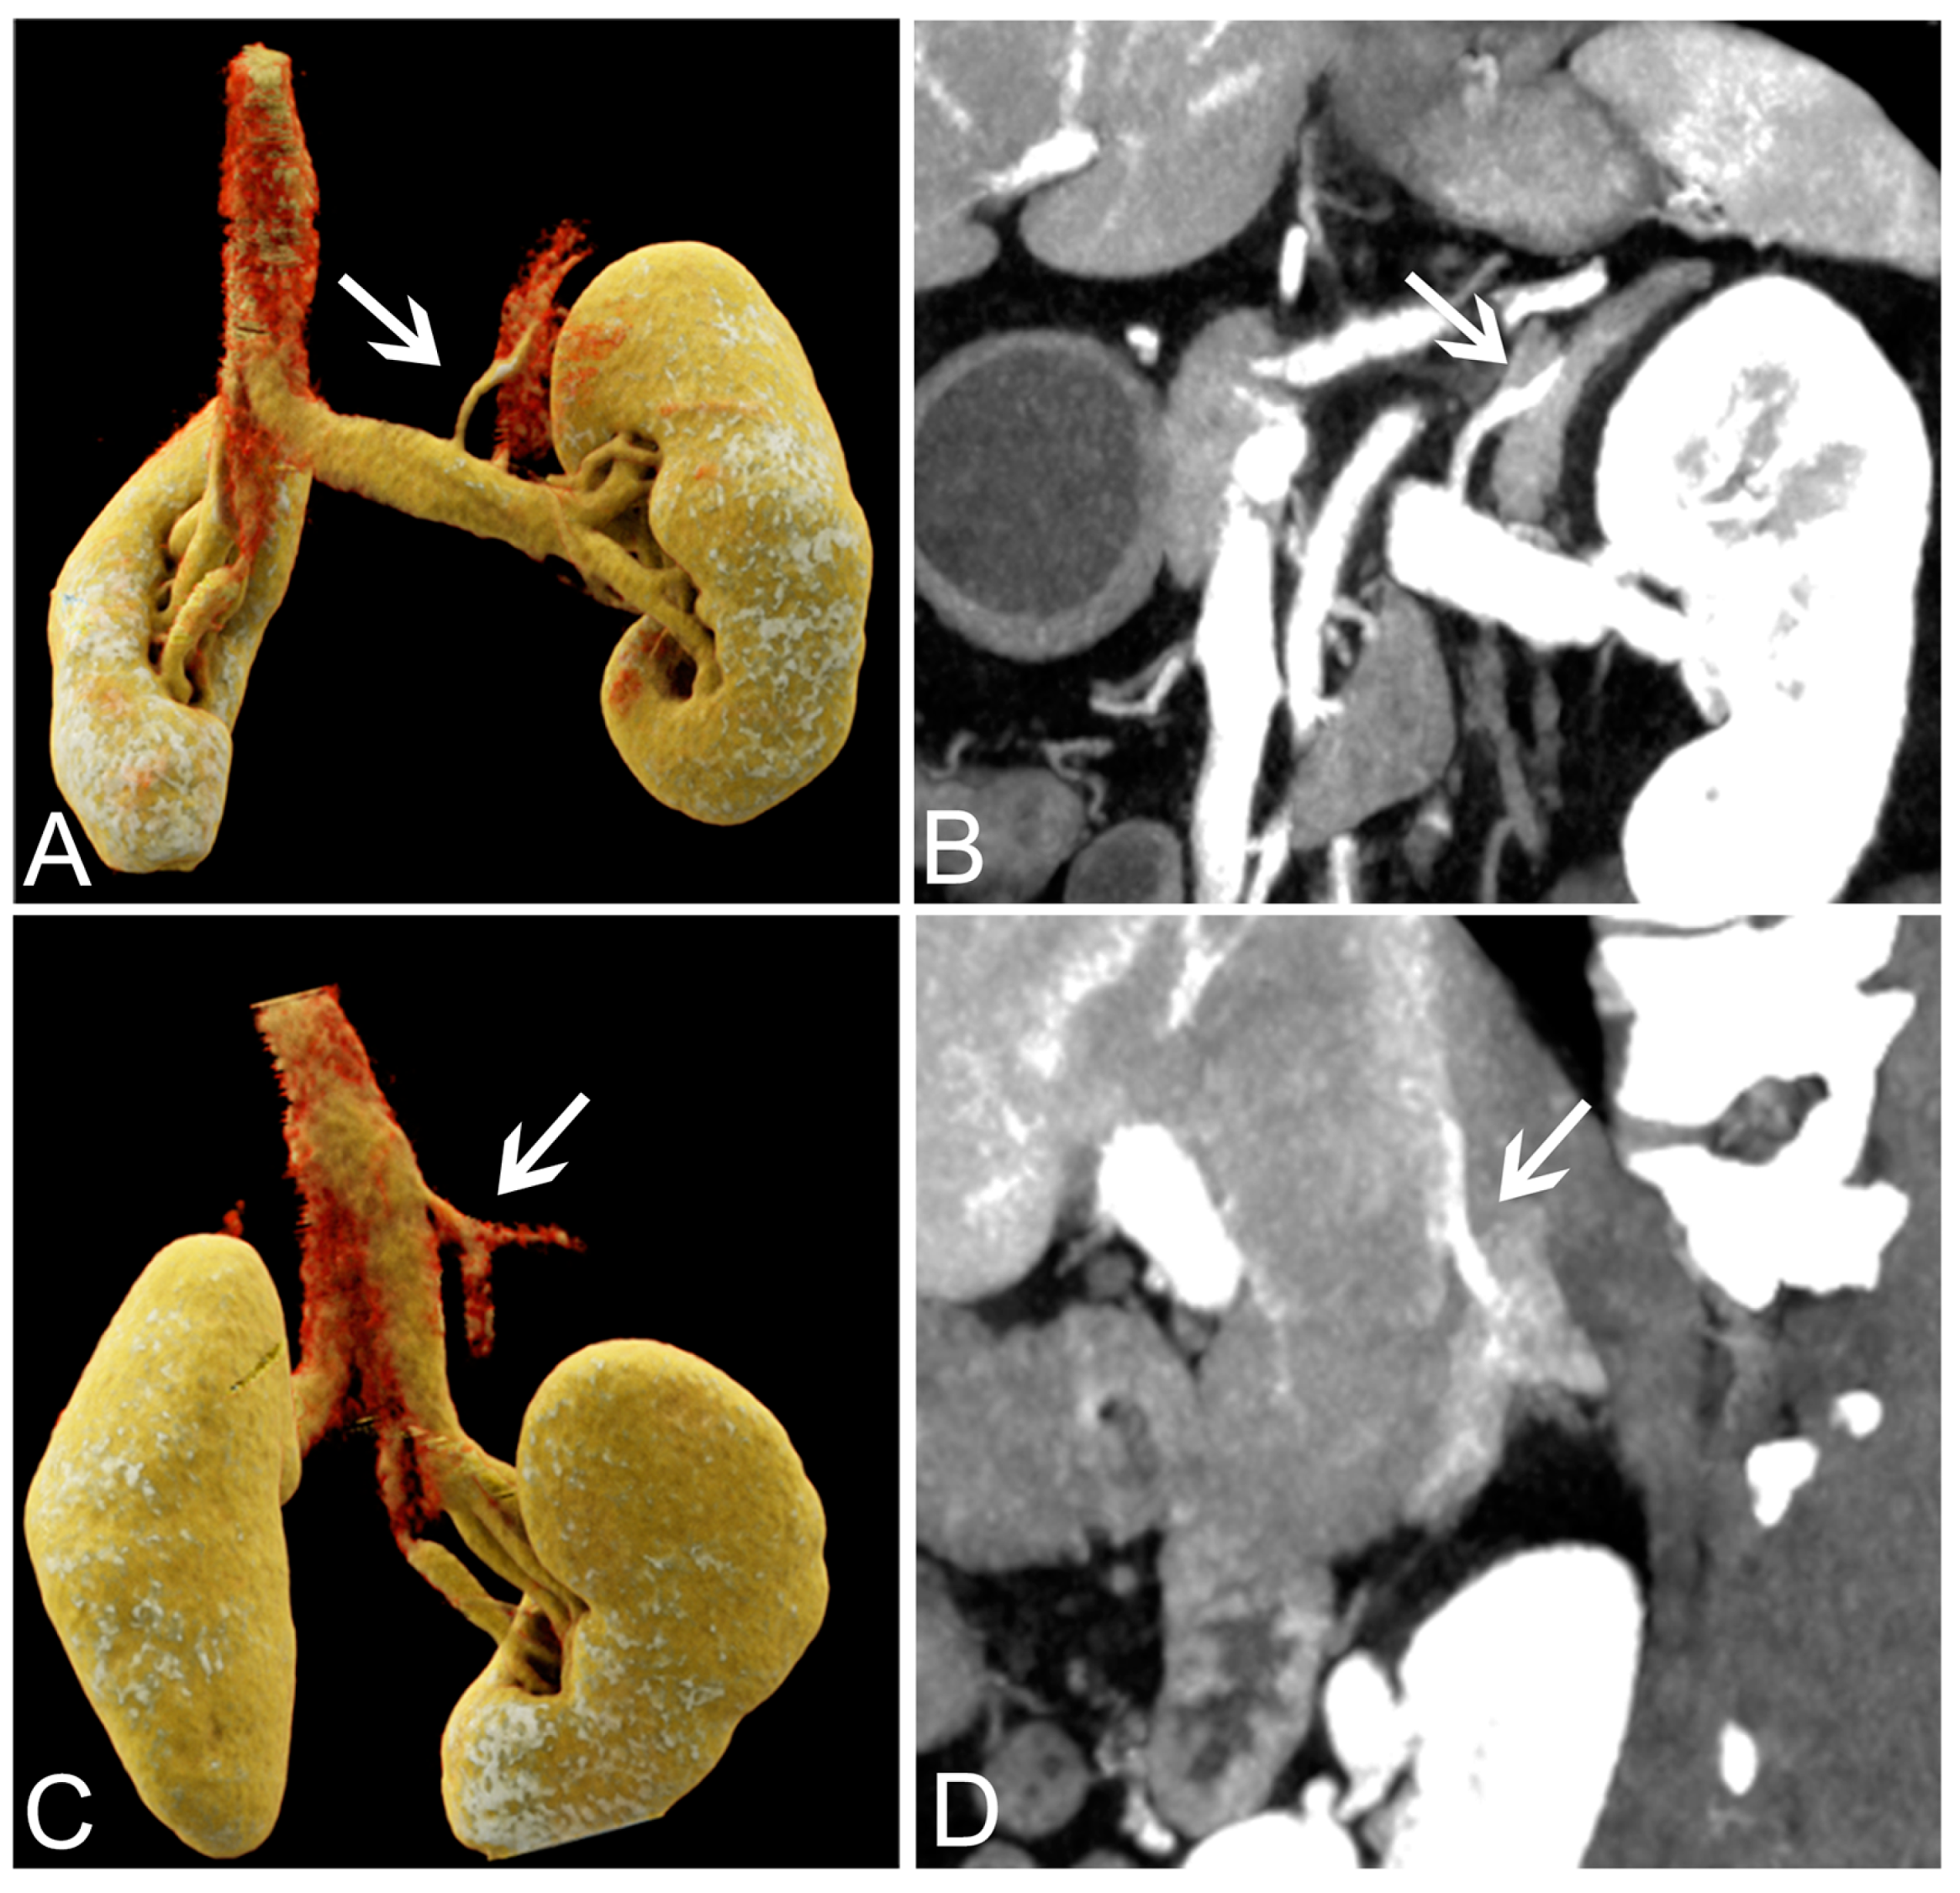

2.5. DECT Subjective Image Analysis

3.4. Success Rate of AVS